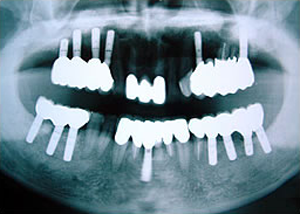

5.終了時レントゲン

治療完了

平成19年5月1日

(治療期間:2年10ヶ月)